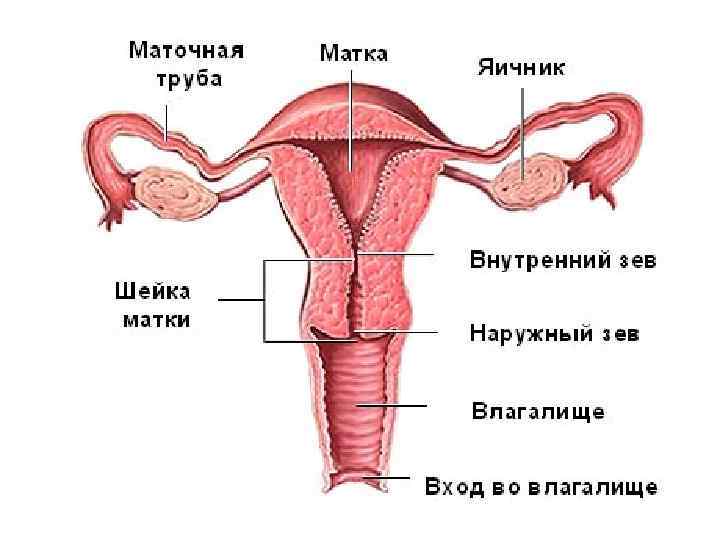

Женские половые органы, organa genitalia feminina

Женские половые органы, organa genitalia feminina

Рис 1 (норма) Гистерограмма: 1 — перешеек матки, 2 — канал шейки матки, 3 — катетер, через который введено рентгеноконтрастное вещество; видно значительное расширение перешейка и канала шейки матки. Рис 2 И стмико-цервика льная недоста точность (insufficientia isthmicocervicalis; Истмико+ анат. cervix uteri шейка матки) -нарушение функции шейки и перешейка матки, проявляющееся зиянием шейки матки, приводящим к самопроизвольному прерыванию беременности; возникает в результате повреждения миометрия или при нарушении гормональной регуляции.

Рис 1 (норма) Гистерограмма: 1 — перешеек матки, 2 — канал шейки матки, 3 — катетер, через который введено рентгеноконтрастное вещество; видно значительное расширение перешейка и канала шейки матки. Рис 2 И стмико-цервика льная недоста точность (insufficientia isthmicocervicalis; Истмико+ анат. cervix uteri шейка матки) -нарушение функции шейки и перешейка матки, проявляющееся зиянием шейки матки, приводящим к самопроизвольному прерыванию беременности; возникает в результате повреждения миометрия или при нарушении гормональной регуляции.